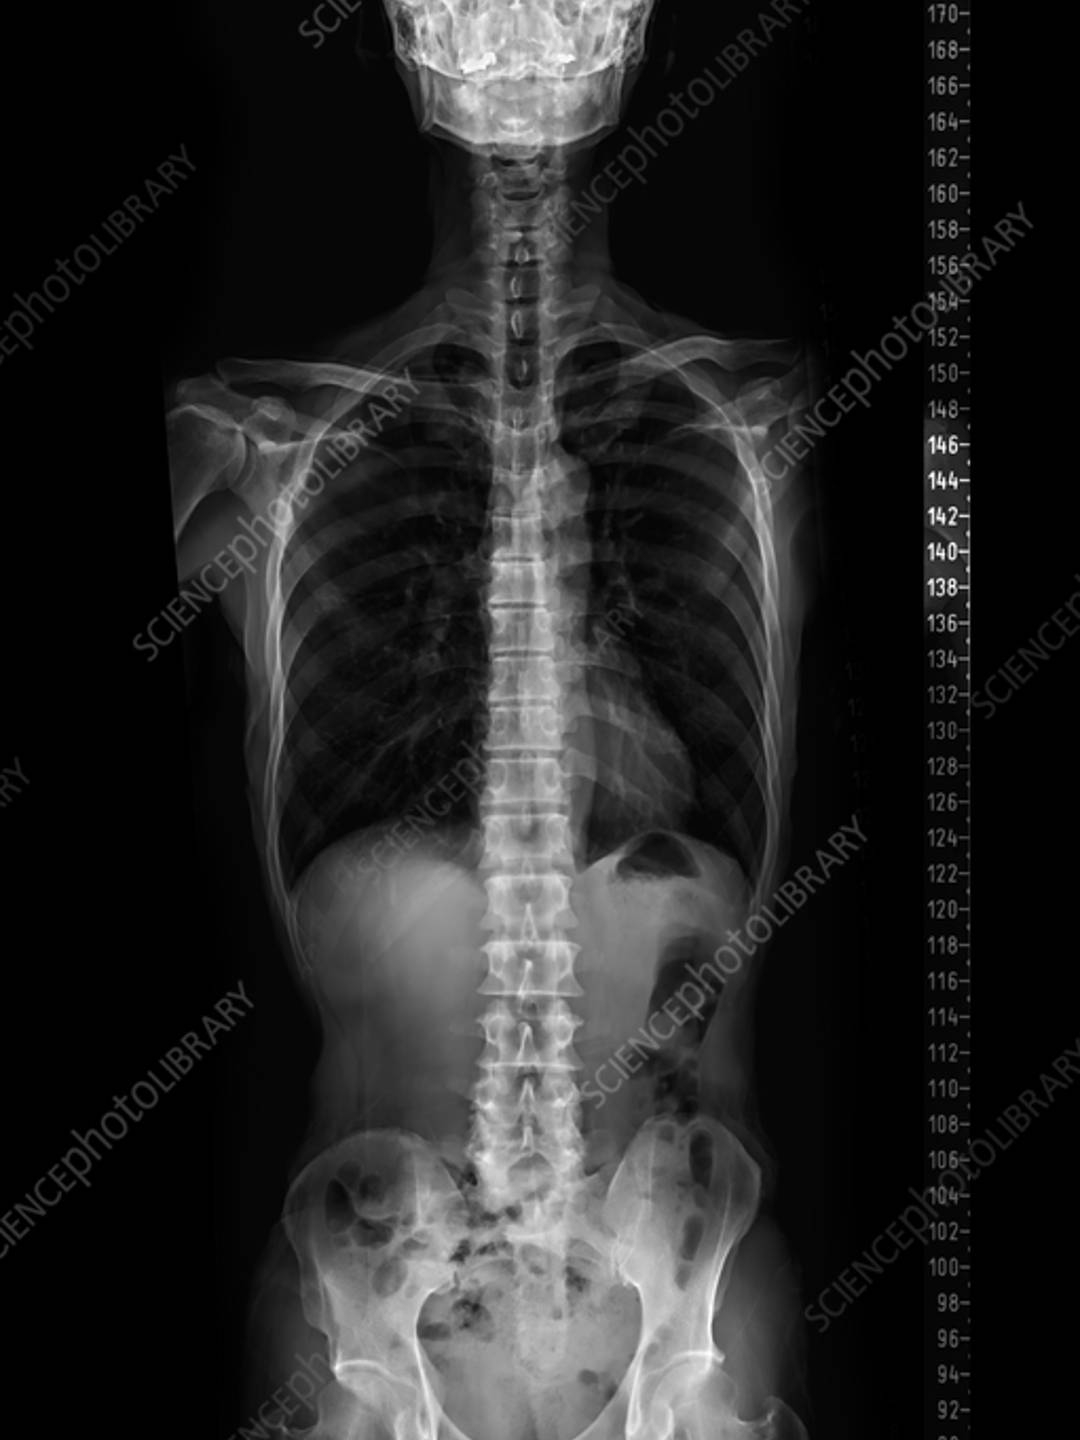

On the left you'll see a healthy spine and on the right is my spine. My spine is clearly doing way too much. It's been like this since at least adolescence. I went to the doctor when I was 19 and they tested a lump on my side for cancer. It wasn't cancer. I asked that they keep testing to find out what it was. They told me it was fat. I asked why it was only on on side. Doctor shrugged and sent me home. One x-ray could have saved me over 20 years of pain and suffering. I'm too tired to be angry. I just want to get well.